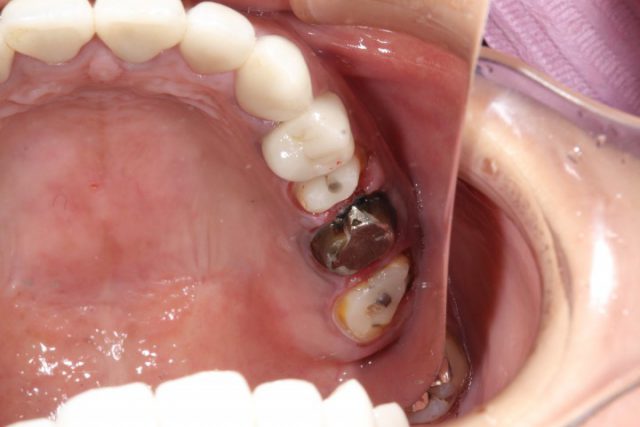

施術中

既存の詰め物をはずし新しく被せ物をする土台を形成していきます。今回は奥歯2本の銀歯用と、奥歯手前2本オールセラミック用の土台を形成しています。